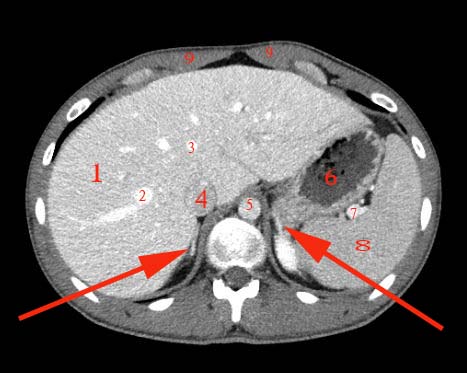

Abdomen axial IQ Test